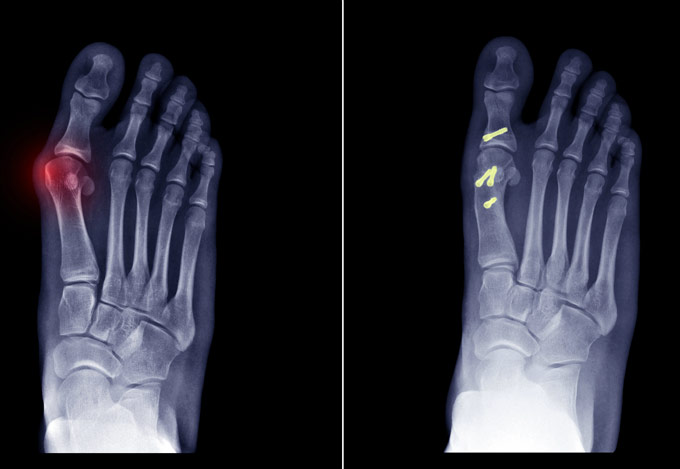

Έχει 5ετή μετεκπαίδευση και εργασία στο Ηνωμένο Βασίλειο ως ειδικός Ορθοπαιδικός Χειρουργός. Έχει εργαστεί στα Ορθοπαιδικά Τμήματα των Νοσοκομείων Southampton University Hospitals NHS Trust, Leeds Teaching Hospitals NHS Trust και στο Northampton General Hospital NHS Trust, με υποεξειδίκευση στη Χειρουργική Ώμου, Γόνατος, Ισχίου, Ποδοκνημικής & Άκρου Ποδός, Ώμου & Αγκώνος και Γενικού Τραύματος Ενηλίκων και Παίδων.

Κατά τη διάρκεια της εργασίας του στο Ηνωμένο Βασίλειο εκπαιδεύτηκε σε σύγχρονες τεχνικές Αρθροσκοπικής Χειρουργικής και Επανορθωτικής Χειρουργικής Ισχίου, Γόνατος και Ώμου. Επιπλέον έχει δώσει πολυάριθμες διαλέξεις και έχει εκπαιδεύσει νεότερους Ορθοπαιδικούς και φοιτητές Ιατρικής. Αξιοσημείωτο και πλούσιο είναι το επιστημονικό του έργο με συμμετοχή σε δεκάδες συνέδρια και σεμινάρια στην Ελλάδα και στο εξωτερικό και έχει πληθώρα προφορικών ανακοινώσεων και δημοσιεύσεων.